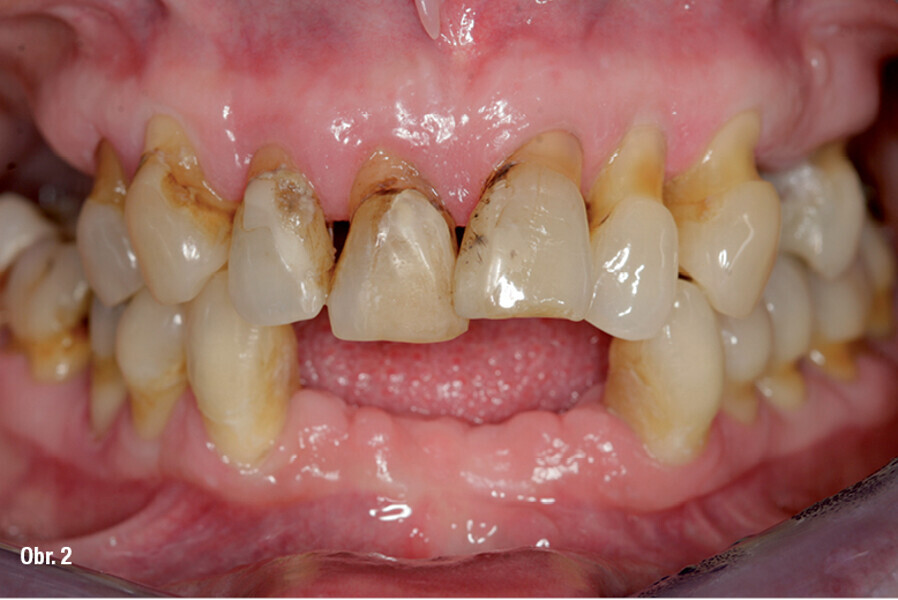

Zubní implantáty – od týmového plánování k esteticky úspěšnému výsledku